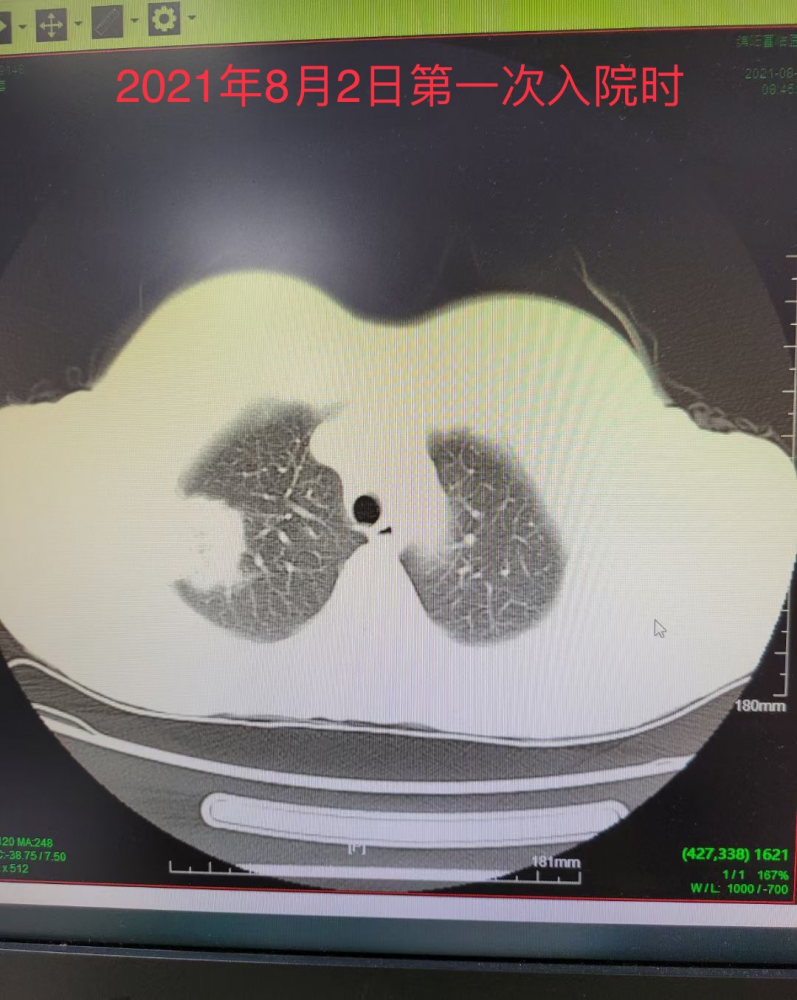

致命的鹦鹉热衣原体重症肺炎急诊医学中心ecmo辅助下救治我院首例鹦鹉

图片尺寸1080x1439